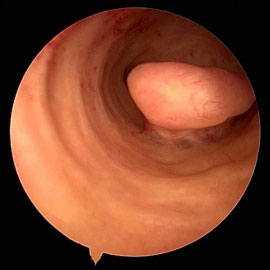

لتشخيص أسباب فشل التعشيش والإجهاضات المتكررة وأمراض جوف الرحم مثل البوليبات والحجب والالتصاقات باطن الرحمية التي تعيق الحمل واستمراره إضافة إلى أمراض بطانة الرحم مع إمكانية إجراء التداخل الجراحي العلاجي المناسب تنظيرياً وبنفس المرحلة.

وقد تم حديثاً إدخال Office Hysteroscopyالمتميز بقطر صغير بحيث يمكن إجراء التداخل الجراحي دون توسيع عنق الرحم وبالتالي دون الحاجة للتخدير العام في كثير من الحالات.